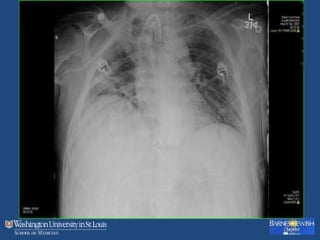

Yes there is VAP

BAL: 78% neutrophils, Klebsiella pneumoniae > 104 cfu/ml.

Treated with appropriate antibiotic regimen and recovered.